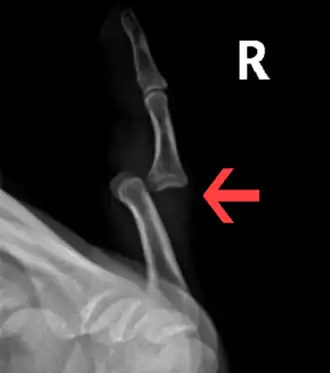

| A traumatic dislocation of the tibiotarsal joint of the ankle with distal fibular fracture. Open arrow marks the tibia and the closed arrow marks the talus. | |